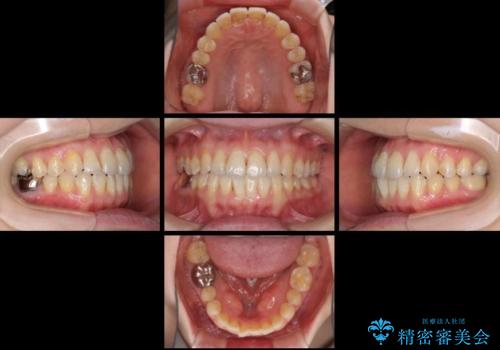

前歯のデコボコを治したい インビザラインによる矯正治療

- 前歯のデコボコを治したいとのことで来院された患者様です。

上下顎ともに歯列全体の後方移動とIPR(歯と歯の間を削る)によってデコボコが解消するように設計し、インビザラインにより治療を行うこととしました。

1日22時間の装着時間をほとんど達成することができず、治療には当初予定の2倍以上の期間を要することとなりました。